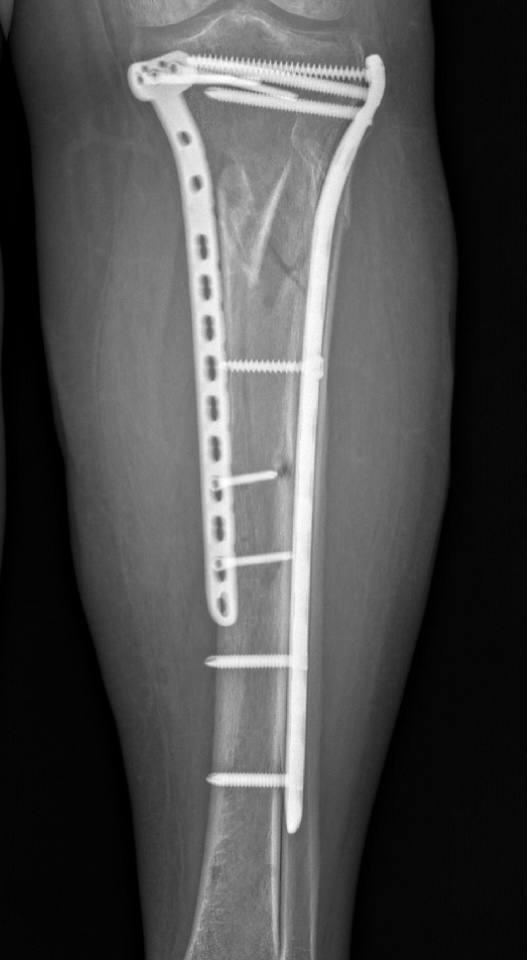

Післяопераційний період проходив без ускладнень і на 10 день після поступлення було проведено наступне етапне оперативне втручання: відкрита репозиція, металоостеосинтез пластинами.